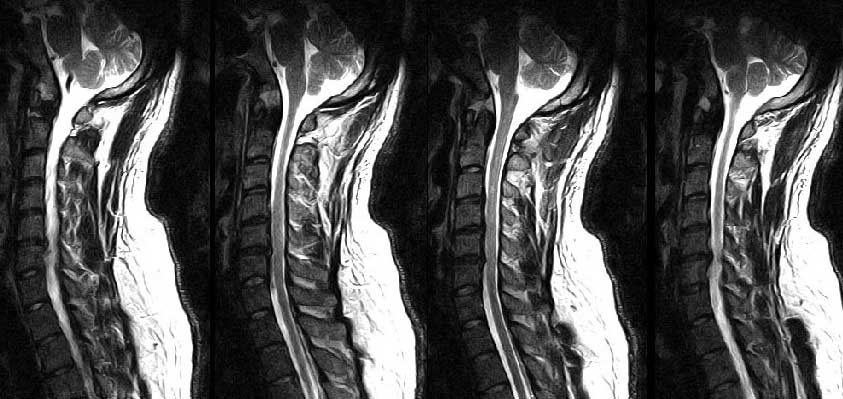

̹ ǥغ ֽ mriԴϴ. ¿ϴ. mri ؾ Ѵٴ ƴϾϴ. ȣǰ ϵ帳ϴ. ù ߶ ħ پٴ ﳳϴ. ñ ǥغ 3 Ͻð ¦ Ÿٸ ־ ġ ϴ. ̸ ǵ Ͻð ˷帰 ƮĪ ϼ. MRI Ÿ ó ϰ Ŀ ִ ڸ ϰ cĿ갡 ˷帰 Ͻø 4 ̳ ˴ϴ. 30и ƮĪ ϼ. ϻ Ÿ ʴ ġر ؾ ǰ? ٴϽô ġᵵ ġر µ ݴϴٸ. ˷帰 ƮĪ Ͻðų ϴµ ξ ð ҿDZ մϴ. ġ Ŀ ƮĪ ֽð ϽŴٸ ߵ Դϴ. ϻȰ Ÿٸ ġ ־ մϴ. ũ ڸ(߹) ġսô ~~ȭ~~ ñ ø ó ̴ּ ȸԲ ߰û ϼŵ ˴ϴ. . . ǥغ ȸԽ ȣϼ̴ Դϴ. 1C.ڵ, 1C.ھ, 1C.̸, 2C.ھȱ , 2C.ڴ , 6C.ڸ , 6C. κ Ḳ , 6C.ھ Ḳ , 6C.ڻ , 1T. κ , 1T.꿪 ĵ 5L.ڴٸ Ʒκ̳ , 5L.ڹ߰ ̳ ȭŸ̳ õ().° ̳ , 㼱 ȸ ȭ ߴ ϵǾֽϴ. Ÿ ֱ ƮĪ ڼ ûϼŵ ˴ϴ. Կġ ϵ ּŵ ū ˴ϴ. ----------23ϰ Ͻ ۼֽ ҰԴϴ.--------------- ũ ǥغ Ͽ no 3496 date 2009-02-02 23:43:56 name (sunwok@hanmail.net) IP: 58.238.94.218 2008 12 22 ũ ҽϴ, Ͽ ʾ ׳ݻ ǥغԸ ˻ 2009 1 ʼ濡 ǥغԸ Ͽ Ͽϴ. ǥغԸ پϴ. ó ǥغԸ ݽŹ Ͽ ǥ ̺ҵ ұ ϰ ֽϴ. ǰ ǥغԸ ڰ µ ϴ. Ը ΰ ϴ. ũ Ͻôºе յνźе Ը ص帳ϴ. մϴ. ---------------------- Ұ http://3wboard.zicoree.com/New_Board/Board/Read.php?Page=1&dummy=1233594982&Board=compill-50-free1&No=3496&Search=&keyword=&period=10000 |